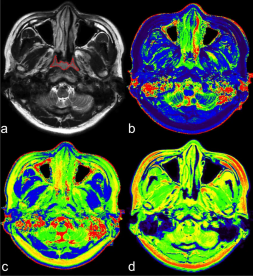

SyntheticMR今天宣布其下一代3D成像解决方案获得了FDA 510(k)许可。SyntheticMR表示,监管机构的点头“标志着定量MRI技术的重大进步。”该公司表示,其SyMRI 3D产品提供了“脑成像中前所未有的分辨率和准确性。”

SyntheticMR公司的商业化产品主要有SyMRI NEURO、SyMRI KNEE 和 SyMRI SPINE 。其中SyMRI NEURO 提供大脑的多种对比图像、组织分割和定量数据已获得 CE 标志和 FDA 510(k) 批准。SyMRI KNEE 和 SyMRI SPINE 为膝关节和脊柱解剖结构提供多种对比图像和定量数据,SyMRI KNEE 和 SyMRI SPINE 已获得 CE 标志。SyMRI是欧洲和美国的注册商标。

SyntheticMR的独特技术可测量大脑的绝对特性,并在单次MR扫描中提供可调节的对比度图像、自动生物标志物分割和定量数据。目前,该公司已与多家医学影像巨头达成合作,包括与 GE Healthcare、西门子医疗、飞利浦医疗、富士胶片、联影、Hyland Healthcare 和佳能医疗系统等,产品销往美国、印度、日本、德国、韩国和中国等。

这一FDA的批准标志着该公司在过去一个月的第二个重要里程碑。该公司最近签订了一份与荷兰医疗科技巨头飞利浦合作以支持其大脑疾病诊断和治疗技术。而SyntheticMR决定与飞利浦合作开发的SyMRI 3D,正是此次获得FDA批准的产品。与飞利浦的扩大合作,也是SyntheticMR公司在建立神经成像新标准的道路上的关键里程碑,旨在进一步提高效率、提升患者诊疗并推动医疗健康领域的有意义的降低成本。